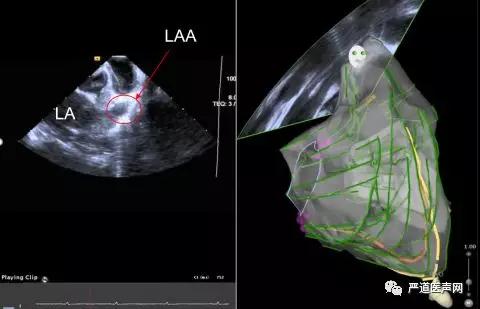

(可判断是否有血栓形成,下图为左心耳内有血栓)

图6 RVOT位置时视野

(左图红圈为左心耳,右图为三维超声建模和扇面展示)